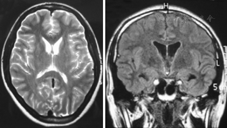

入院体检:对答切题,查体合作,营养中等,自动体位,舌体前部多处咬伤,继发性溃疡,左侧第2磨牙处口咽壁可见1个绿豆大小溃疡,咽部无充血,扁桃体不肿大,心肺腹部检查无异常,脊柱、四肢无畸形。神经系统体检:神清,言语不利,构音障碍,言语讷吃,智力正常[简易精神状态检查量表(MMSE)得分29分],口唇咂动、舌体咬伤频繁,为避免咬舌和舌体不自足活动,患者口腔中放置一团毛巾,眼动充分,双瞳孔等大等圆,直径3 mm,对光反射存在,无眼震、复视,双侧鼻纹对称,伸舌居中,悬雍垂居中,双侧软腭上抬无力,咽反射明显减弱,四肢肌力Ⅴ–级,四肢肌张力减低,面部、躯干、四肢浅感觉正常,音叉振动觉正常,腱反射明显减弱,病理反射未引出,行走协调性差,颈软无抵抗,脑膜刺激征阴性,共济运动协调。辅助检查:血、粪、尿常规正常;血生化检查:电解质、血糖、尿酸、肾功能、血脂正常;ALT 48 U/L,AST 80 U/L,乳酸脱氢酶459 U/L,肌酸激酶同工酶(CK–MB)47 U/L,α–羟丁酸脱氢酶393 U/L,均升高,肌酸激酶(CK)显著升高达2 806 U/L。心功能三项:高敏肌钙蛋白T正常,肌红蛋白72.49 μg/L(升高),N末端脑钠肽原246.70 ng/L(升高)。红细胞孵育渗透脆性试验阴性。ESR、抗链球菌溶血素O、类风湿因子、C反应蛋白正常。体液免疫五项(IgG、IgA、IgM、补体C3、补体C4)正常。钩端螺旋体IgG抗体、抗髓过氧化物酶抗体、抗蛋白酶3抗体阴性。结核分枝杆菌TB–DOT试验阴性。肝病寄生虫全项(–),广州管圆线虫抗体(±),日本血吸虫IgG抗体(–)。抗–HCV、抗–HIV、HIV–Ag、梅毒螺旋体抗体阴性。甲状腺功能正常。促卵泡激素、黄体生成素、雌二醇、睾酮均正常,催乳素38.35 μg/L(升高)。肿瘤标志物、肝炎分型正常。腰椎穿刺:脑脊液压力155 mmH2O(1 mmH2O=0.009 8 kPa),无色透明,红细胞40×106/L(穿刺伤),白细胞0,潘氏试验阴性,葡萄糖3.56 mmol/L,LDH 14 U/L,蛋白900 mg/L,腺苷脱氨酶0.10 U/L,新型隐球菌涂片、脑脊液结核菌涂片均阴性,脑脊液培养未见细菌和真菌生长。X线胸片、心电图、脑电图正常。经颅多普勒示:左侧大脑前、后动脉血流速度稍增高。消化系、泌尿系、妇科B超正常。肌电图示多发性周围神经损害。眼科裂隙灯下未见角膜K–F环。头颅MRI显示双侧尾状核头部萎缩(图1)。患者第1次外周血涂片高倍镜下见棘红细胞,占红细胞计数的50%,第2次外周血涂片棘红细胞占红细胞计数25%。患者父亲(50岁)、母亲(48岁)、姐姐(27岁)外周血涂片均可见棘红细胞,分别占红细胞计数的30%、25%和2%(图2)。患者诊断为舞蹈病–棘红细胞增多症(chorea–acanthocytosis, ChAc)。

本例特点为:(1)青年女性,缓慢起病,逐渐进展;(2)口舌不自主多动,经常咬伤舌体并继发舌体口腔溃疡,流涎,言语含糊不清,行走不稳,侧向倾倒,癫痫发作,呈强直阵挛发作,咽反射减弱,肌张力减低,腱反射减弱;(3)父母非近亲结婚,家族中无类似疾病患者,父亲家系和母亲家系未见其他患病者,父母为可疑携带者,符合常染色体隐性遗传的特点;(4)乳酸脱氢酶、肌酸激酶、催乳素增高,肌电图示多发周围神经损害;(5)患者外周血涂片查到大量棘红细胞,其父母外周血均可查到多量棘红细胞;(6)颅脑MRI扫描显示尾状核萎缩;(7)检测到突变基因在VPS13A。

ChAc的临床特征以锥体外系症状、体征及血液学、神经影像改变的特点为主[4,5,6,7]:(1)发病年龄8~62岁,平均32岁,男多于女;(2)以舌肌、口唇和咀嚼肌的不自主运动为特征,吐舌,进食性肌张力障碍,常伴肢体或躯干的舞蹈样动作、咬舌、咬唇;(3)癫痫、认知障碍和精神异常;(4)肌张力减低,腱反射减弱或消失,肌电图示周围神经损害;(5)涉及多系统;(6)外周血棘红细胞增多(占5%~50%,需除外肝脏疾病、脾切除术和溶血性贫血);(7)血清肌酸激酶增高;(8)CT或MRI示侧脑室前角增宽,尾状核萎缩。